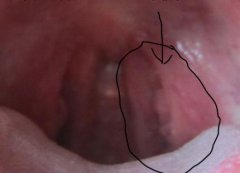

首先要祛除疣体,因为早期病情发展较慢,有三个月左右的潜伏期,病毒扩散较慢,这是治疗的最佳时期,用药物涂抹于患处,经过表皮吸收后直接作用于病毒细胞核,将人体皮肤基底层、生发层细胞和神经节内的病毒或病菌进行完全灭杀,迅速消除尖锐湿疣临床症状。